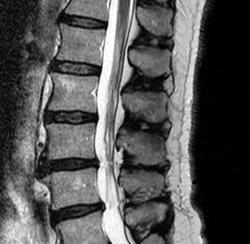

My MRI: The Awful Truth

SONY DSC [Image from Wikipedia]

“Well”, he said, “see these little pinches in between your L-4 and L-5?”

[This is not my spine. Image from Wikipedia]

“Of course I see them”, I said looking at a screen that resembled a NASA image of the far side of Charon, a moon orbiting Pluto.

“But, something worrisome is showing up here,” he said. “See the area just to right of my pencil point?”

“Well, right down here near the end of your endothelial membrane, I see a disturbing sequence beginning to take form.”

“Well, I see a growing sense of self-doubt and insecurity,” he said. “See here?”

“Over here, near your Lumbo-sacral spine, is a large mass of guilt and misgivings. Alongside that is a well of worry and loneliness.”

“But there is also a distinct lack of morality, pleasure and sincerity,” he said, “and over here, see, there is growing sense of self-doubt, a mass of existentialism and nihilistic thought, as well as an approaching feeling of fear and trembling.”

“You have age appropriate degeneration of the lower spine. Live with it.”